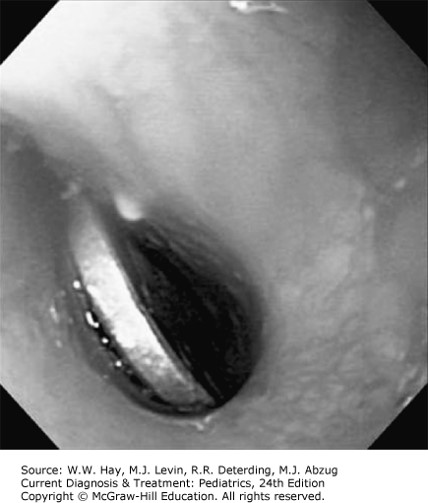

Luckily, most foreign bodies are able to pass through a child's digestive system on their own. According to Chapter 21: Gastrointestinal Tract in Current Diagnosis & Treatment: Pediatrics, 24e, esophageal foreign bodies should be removed within 24 hours of ingestion and 80-90% of foreign bodies pass spontaneously while only 10%-20% require endoscopic or surgical management.

Figure 21-3 of the Gastrointestinal Tract chapter shows a coin lodged in the esophageal lumen.